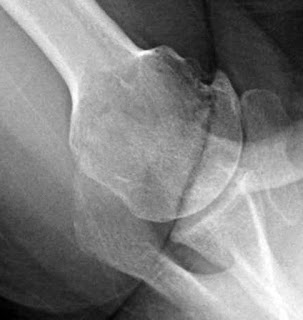

Complete and functional bony malunion of the humeral or femoral diaphysis is occasionally seen following conservative treatment of overridden midshaft fractures. Treatment is nearly always nonoperative in younger patients due to the remodeling potential of the proximal humerus. In younger, more active patients, reduced function and pain that accompany select proximal humeral malunions are generally poorly tolerated.

S42.391p is a billable diagnosis code used to specify a medical diagnosis of other fracture of shaft of right humerus, subsequent encounter for fracture with malunion. Malunion of the articular surface of the humeral head can lead to pain, chronic degenerative changes secondary to joint incongruity and mechanical block to the range of movement. Rature are incomplete, sometimes confusing and controversial. Symptoms of a malunion reduced function in the injured area Pediatric proximal humerus fractures are a relatively common physeal and metaphyseal fracture of the proximal humerus seen in children with a peak age of 15 year of age. Malunion is defined as the healing of bones in an abnormal position. At 6 months, the fracture had fully united with no loss of reduction. Biomechanical failure can be caused by any of a number of incidents that prime the fracture for instability and consequent hardware failure, resulting in malunion and nonunion. The cause of a humerus fracture is usually physical trauma such as a fall. Not many people will answer if you don't give detail, you aren't saying much with this question. Malunion of a proximal humerus fracture is difficult to manage once bone union has been achieved in a wrong position. Leaving it in place may lead to cortical atrophy and a higher risk of. In cases of a nonunion of a surgical neck fracture, the constant motion through the fracture site can cause the medial cortex of the humeral shaft to cavitate the humeral head. Complete and functional bony malunion of the humeral or femoral diaphysis is occasionally seen following conservative treatment of overridden midshaft fractures. Can be partially compensated for by remodeling of the bone (except for rotational malunion) refracturing. The authors recognize the necessity of a new systematic approach. When the broken bone heals in an unusual position it is referred to as a malunion.